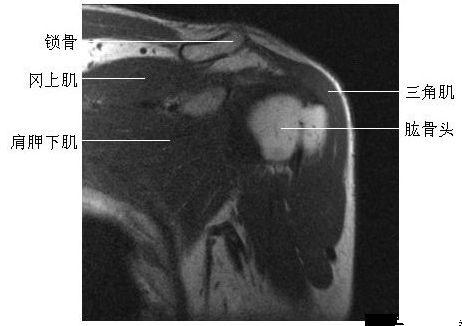

肩关节冠状面(三)